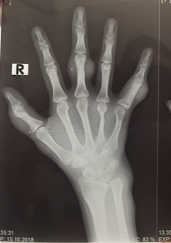

X-Rays films of the right hand: No erosion of the bone.

Abnormal atrophic metatarsal number 4.